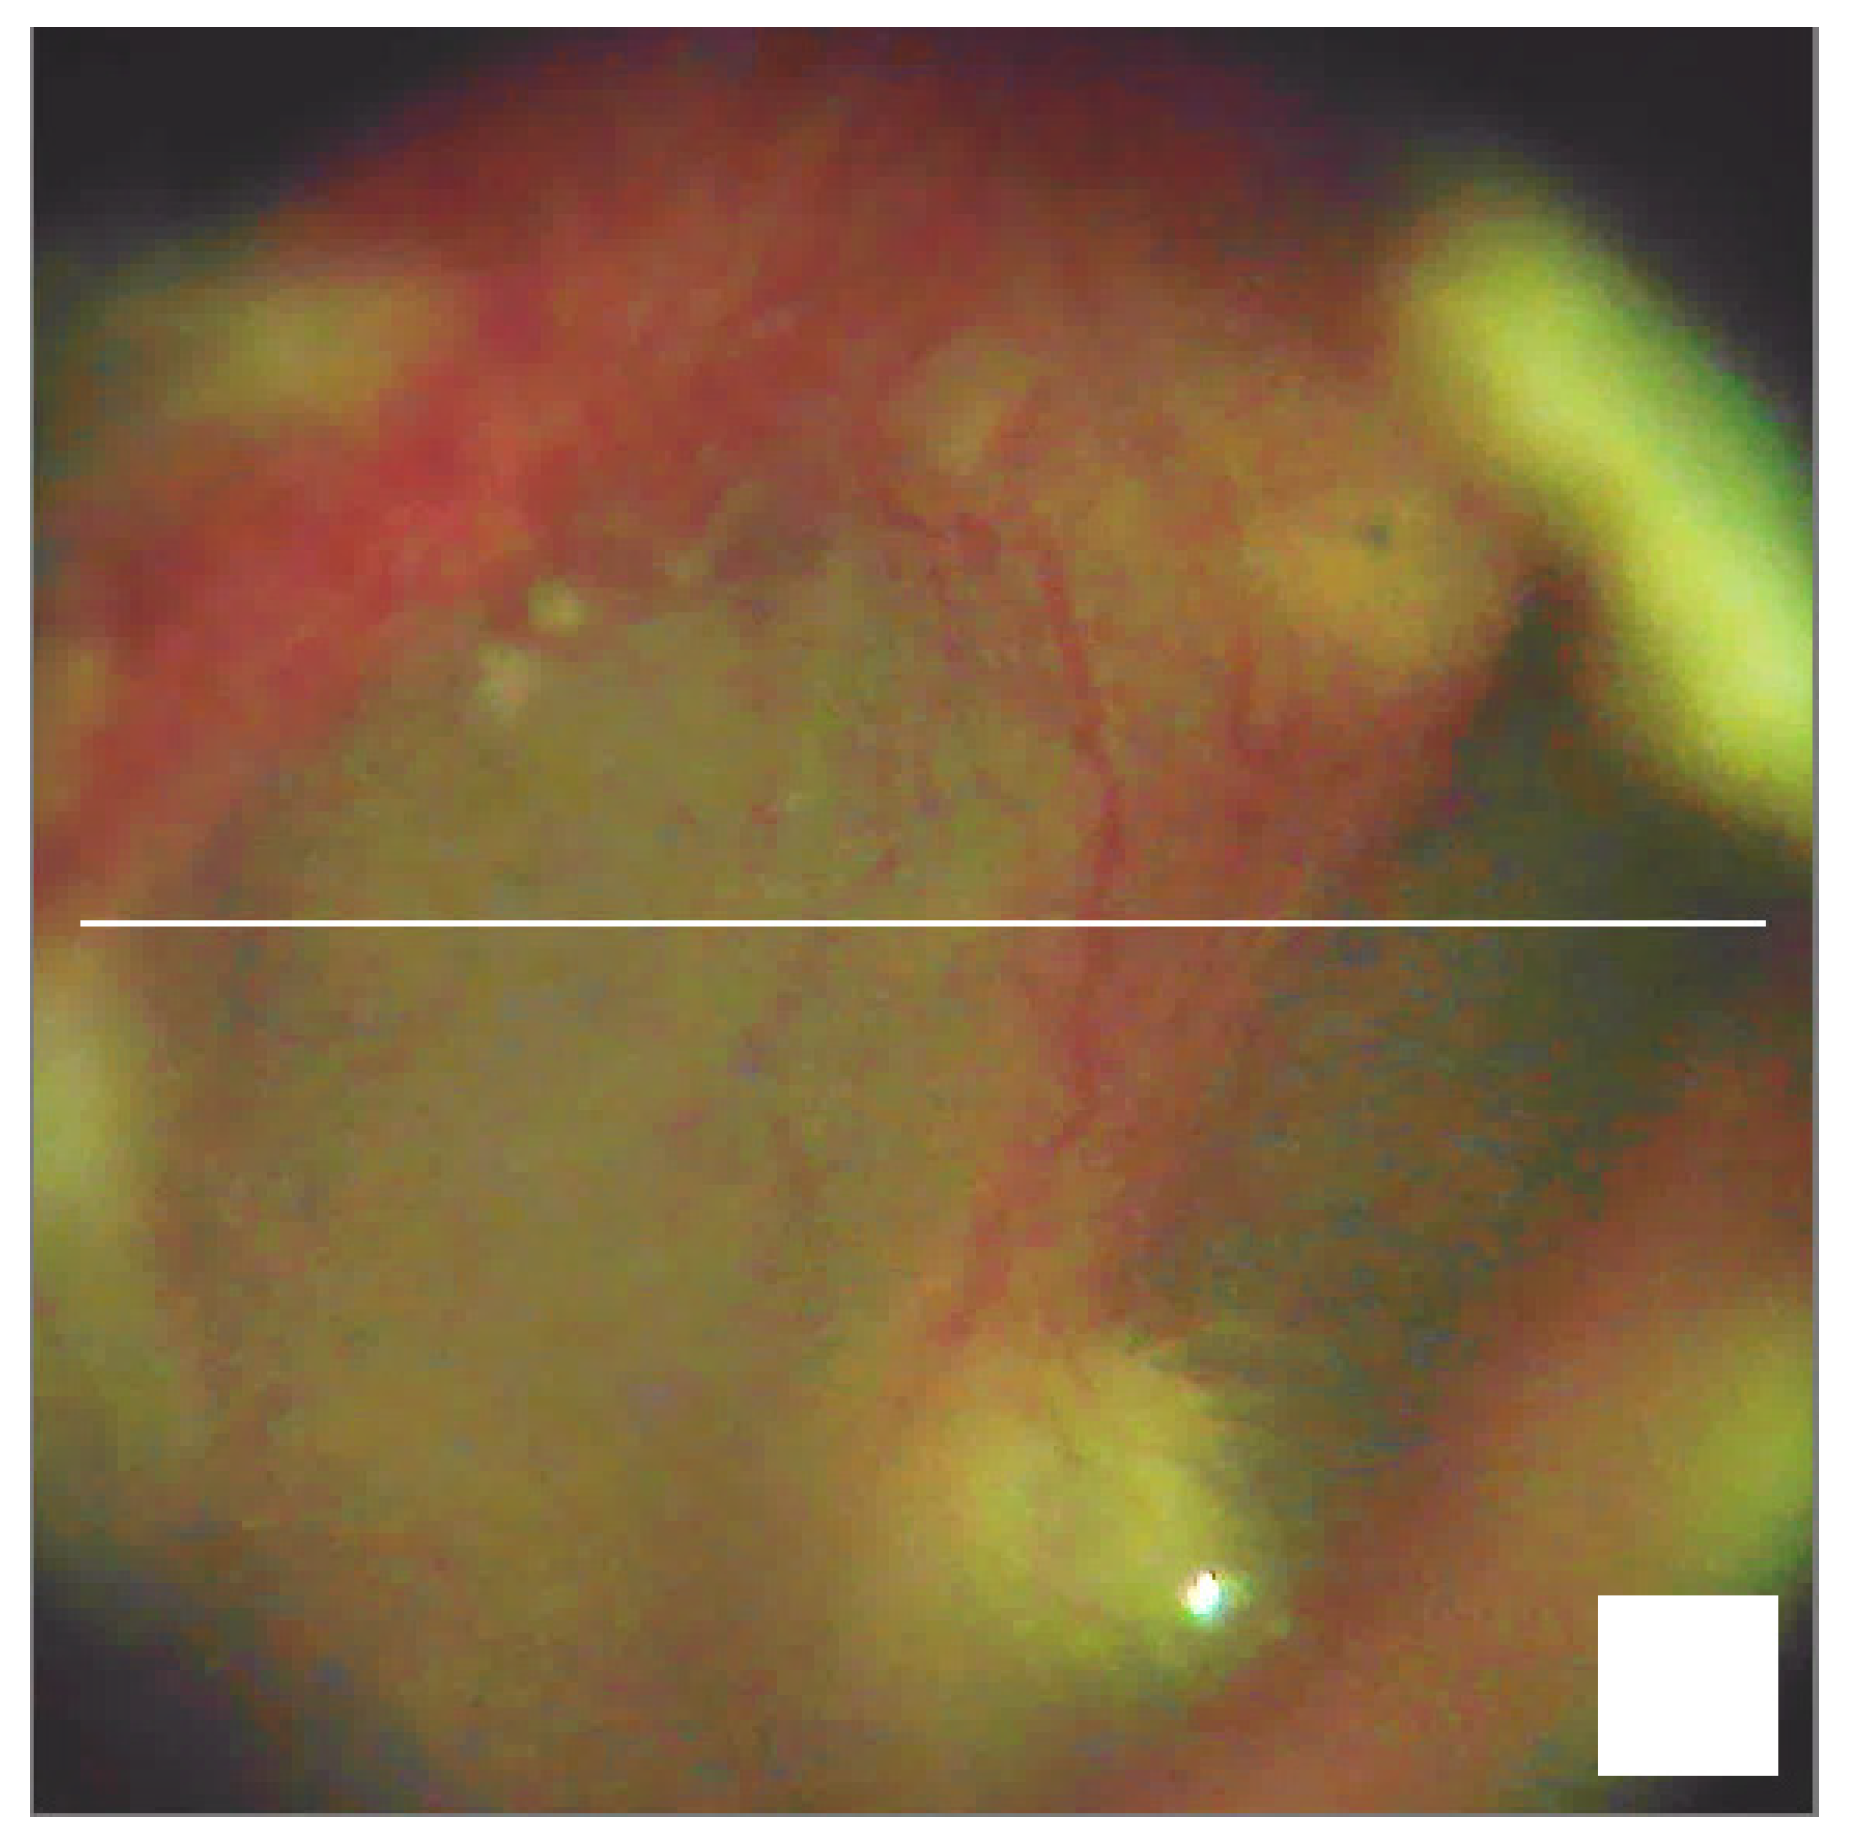

3. Real-Time Visualization Routine for the Region-of-Interest Search

4. The Result of 3D Visualization of the Eardrum